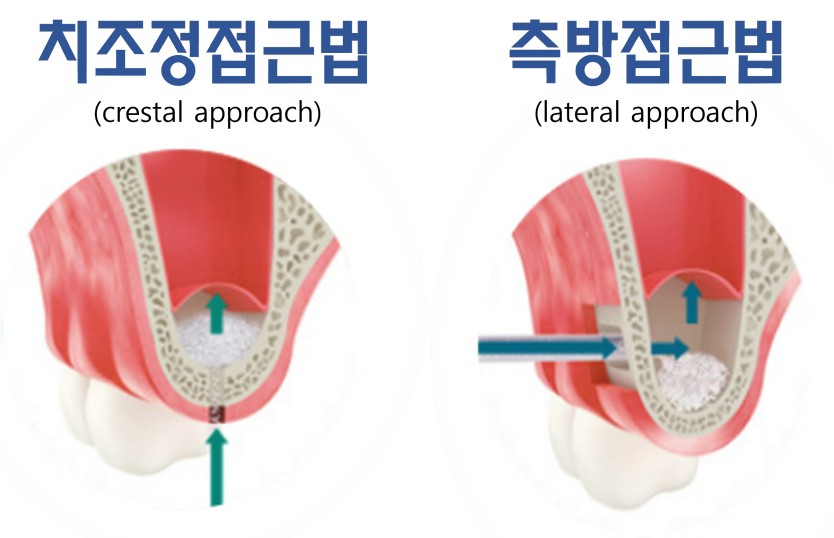

<여기서 상악동 거상술이란??>

우선 상악동이란 광대 뼈 속에 위치한 공기 주머니를 뜻하며

위 치아 치주염이 심했던 경우, 이가 빠진지 오래된 경우, 상악동이 쳐져있는 경우

등 다양한 원인으로 상악동이 내려와 치조골이 얇아 질수 있습니다

이런 경우 행하는 술식을 상악동 거상술 이라고 합니다

환자분의 상태에 따라 필요한 술식을 선택해 진행하게 되고

이로 인해 충분한 치조골 이식과 임플란트의 공간을 확보하게 되며

보다 안정적인 임플란트 사용을 기대할 수 있습니다